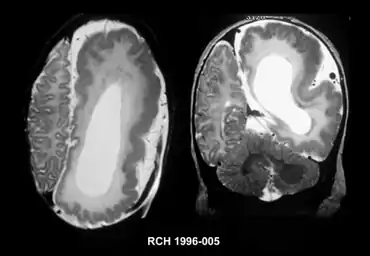

Imaging features of hemimegalencephaly- Axial left, coronal right

It should be suspected in infants or children with intractable, frequent seizures.[4] On a CT scan, the affected part is distorted and enlarged.[9] It can be diagnosed prenatally, but a lot of cases go undiagnosed until seizures begin. Ultrasound can display asymmetrical brain hemispheres.[5]